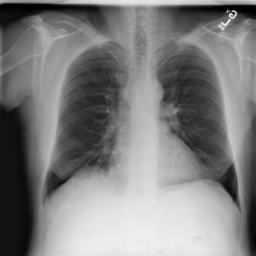

Figure 2: Examples of normal vs. abnormal images of considered datasets. Natural images: (first row) cars vs other classes of CIFAR10 dataset [1], (second row) digits “0” vs digits “1” – “9” of SVHN dataset [2]. Medical images: (third row) healthy tissue vs. tissue with metastases in H&E-stained lymph nodes images from Camelyon16 challenge [3], (fourth row) normal chest X-rays vs. chest X-rays with abnormal findings from NIH dataset [4].

Anomaly detection is a crucial task in the deployment of machine learning models, where knowing the “normal” data samples should help spot the “abnormal” ones [5, 6]. If an input deviates from the training data substantially (e.g., the input belongs to a class not represented in the training data), it is usually impossible to predict how the model will behave [7, 8]. This trait is especially important in high-consequence applications, such as medical decision support systems, where it is especially vital to know how to recognize the anomalous data. Identification of rare occurrences is another important application where anomaly detection is useful. For example, in pathology, where labeling diverse microscopy datasets is both time-consuming and expensive, the rare types of cells and tissues require specialized expertise from the annotator [9, 10]. Forthright anomaly classification and segmentation algorithms are typically prone to mistakes either because of the lack of sufficient annotation (thousands of labeled examples needed for supervised models) or because of the lack of representative data altogether (e.g., the case of some rare pathologies). Moreover, these algorithms are affected by the need to deal with very unbalanced and apriori noisy data, frequently leading to inaccurate results (e.g., the findings on chest x-rays can be so subtle that they can lead to disagreement in the interpretation [11, 12]). Because the normal cases greatly prevail over the abnormal ones, the anomaly detection could alleviate the annotation burden by automatically pointing to the rare samples.

In recent years, deep learning techniques achieved important advances in image anomaly detection [13, 14, 15, 16, 17, 18, 19, 20, 21]. However, these efforts were primarily focused on artificial problems with distinct anomalies in natural images (e.g., outliers in images of “cars” in the CIFAR10 dataset [1], see Figure 2). The medical anomalies, however, differ from those in the natural images [15, 19, 22]. Contrary to the natural images, the anomalies in the medical domain tend to strongly resemble the normal data. For example, detection of obscure neoplasms in chest X-rays [4] and of metastases in H&E-stained lymph node images [3] manifest a blatant challenge at hand, with the anomalous tissues being barely different from the normal ones (see Figure 2). Although deep learning has proved useful for a variety of biomedical tasks [23, 24, 25, 26], only recently, a few groups started dedicating their effort to the anomaly detection problem [15, 19, 27]. However, to the best of our knowledge, a thorough comparison of the state-of-the-art (SOTA) solutions in the medical domain is still missing despite the pressing demand and the prospective clinical value.

Anomaly Detection on Chest X-Rays

Chest X-ray is one of the most common examinations for diagnosing various lung diseases. We considered the task of the recognition of fourteen findings, such as Atelectasis or Cardiomegaly, on the chest X-rays in the NIH dataset (ChestX-ray14 dataset) [4] (Figure 2). Searching abnormalities on a chest x-ray is challenging even for an experienced radiologist since abnormality may occupy only a small region of lungs, or be almost invisible. The dataset consists of 112,120 frontal-view images of 30,805 unique patients: 86523 for training, 25595 for evaluation. We split the dataset into two sub-datasets having only posteroanterior (PA) or anteroposterior (AP) projections, because organs on them look differently. We tried different preprocessing during the hyperparameter search: rescaling to 256x256, 128x128, and 64x64 and histogram equalization, central crop (3/4 of the image size) to delete “noisy” borders. We considered images without any disease marker as “normal” and used them for training. Abnormal images for hyperparameter searching comprised of the training images of the most frequent disease (‘Infiltration’) out of fourteen possibilities. We also evaluated model on subset containing “clearer” normal/abnormal cases (provided by  [22]). This subset consists of 4261 normal images for training, 849 normal and 857 abnormal images for validation, and 677 normal and 677 abnormal images for testing.